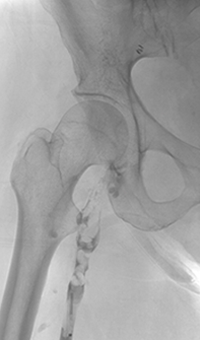

Case CLI with right foot ulcer thrombectomy: Posterior and anterior tibial

Case CLI with Right Foot Ulcer Thrombectomy pre-procedure arteriogram.

Arteriogram of posterior and anterior tibial post-CDT

PT and AT remained occluded following overnight CDT infusion of lytic

Case CLI with Right Foot Ulcer Thrombectomy post-AngioJet Solent Dista.

Post-AngioJet™ Solent™ Dista thrombectomy with PowerPulse™ delivery

AngioJet Solent Dista Catheter used in Power Pulse mode in both AT and PT. 30 min dwell in  AT and 45 min dwell in PT. Followed by Solent Dista Catheter used in thrombectomy mode

Case CLI with Right Foot Ulcer Thrombectomy post-procedure arteriogram.

Post-procedure arteriogram

Image following ballooning of small focal lesion in PT